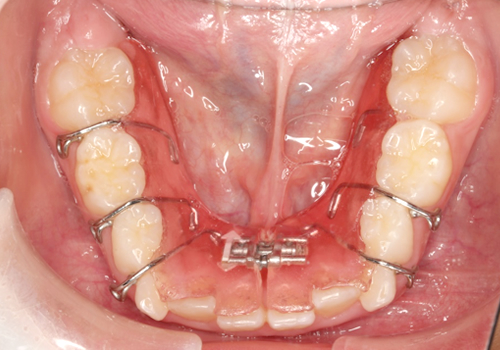

症例03. 急速拡大装置

上あごの幅を拡げるための装置です。正中口蓋縫合と呼ばれる骨の結び目に作用し、骨ごと拡大します。

| 治療内容 | 1:上あごが狭く、交差咬合になっている 2:朝夕2回スクリューを回してもらう 3:正中は離開し、幅が拡がったのがわかる |

|---|---|

| 期間 | 半年 |

| 費用 | 300,000円+税 |

| リスク | 拡げた際の痛みが数日出ることがあります。 |